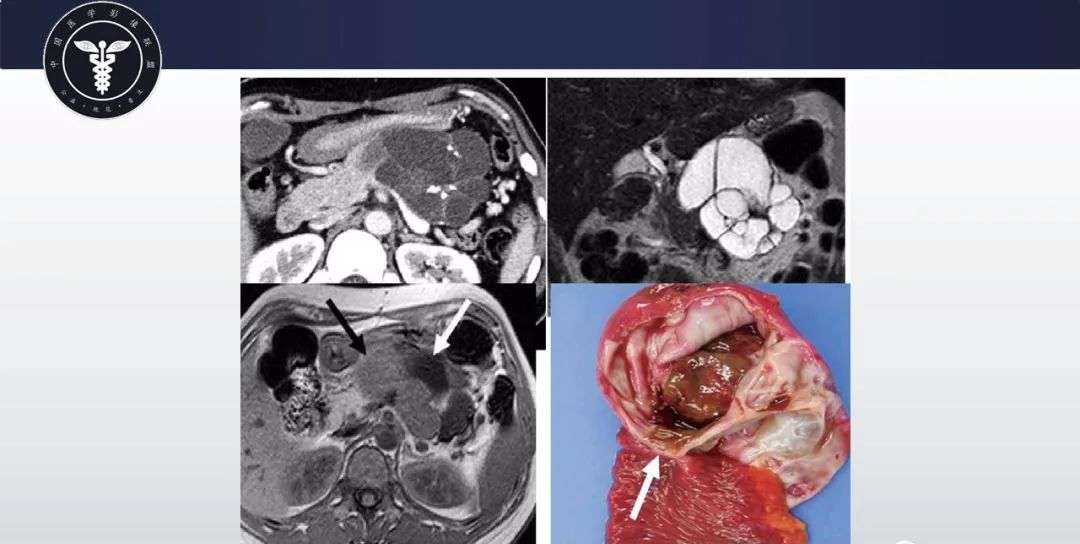

【病例】胰腺血管瘤1例CT及MR影像-5

【病例】胰腺血管瘤1例CT及MR影像-6

【病例】胰腺血管瘤1例CT及MR影像-7

【病例】胰腺血管瘤1例CT及MR影像-8